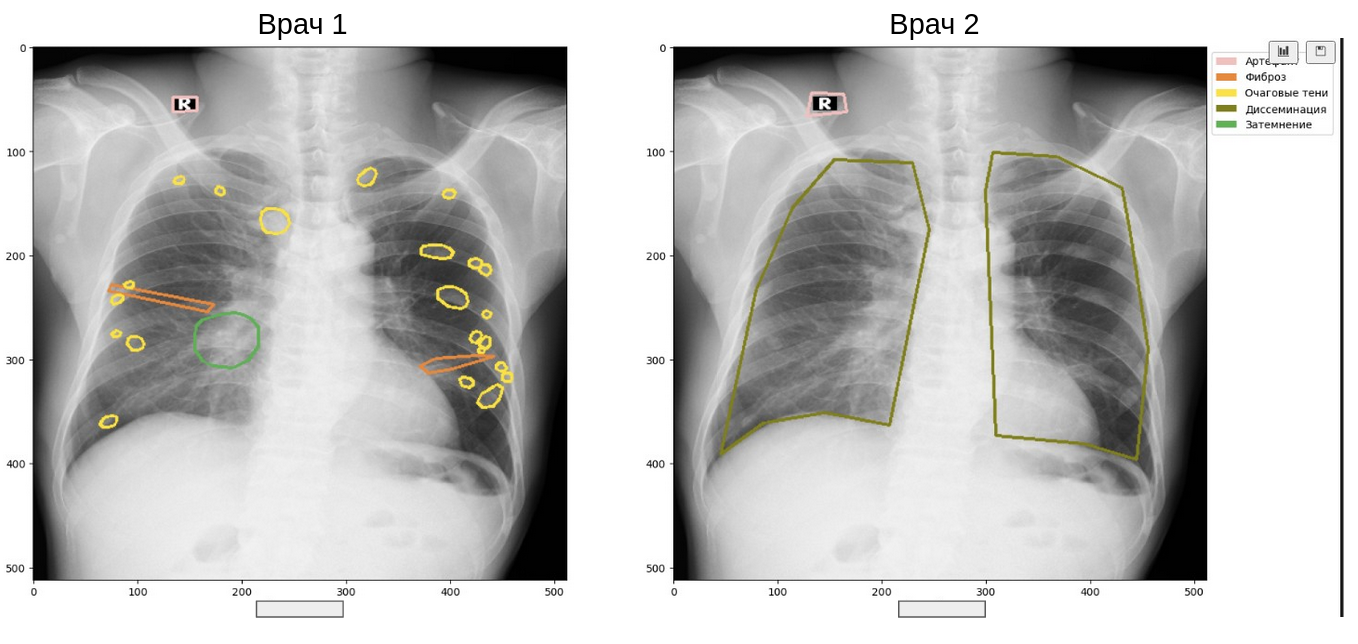

Если вы смотрели хоть одно моё выступление, то, наверняка, слышали нытьё про расхождения в разметке врачей. Например, такие:

Верифицированных данных (где диагноз подтверждён другим анализом или событием) в медицине немного, поэтому приходится жить с тем, что на одно исследование у нас обычно есть 2-5 вариантов разметки. Как считать метрики качества какой-нибудь модели детекции или сегментации в таком случае?